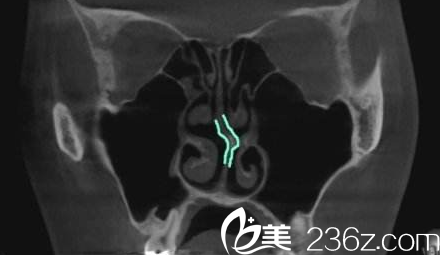

nplus医院其实在国内的宣传也并不多,但因隆鼻方面的技术特别擅长,所以有许多想隆鼻的朋友都知道他们家医院。他们家只有一位代表院长尹贤哲,也是擅长鼻整形、鼻修复。韩国N Plus整形外科在鼻修复方面,推崇的就是首先进行CT检查,了解求美者的鼻内构造,鼻软骨是否有歪斜,是否有组织破裂等等,在此基础上手术就更加游刃有余。